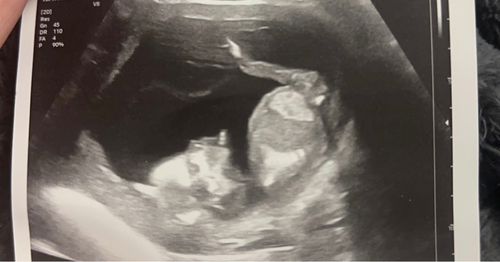

Wat ze hebben gezien op de echo:

- volledige AVSD hartafwijking

- verdikte nekplooi van 4,7mm

- vocht in hoofd tot en met de oksel

- 2 cystus in de hals

- vergrote nierbekken

- grote teen wijkt flink af van de andere tenen

En ik ben op dit moment 17 weken zwanger.. de kans is groot dat er alleen maar nog meer afwijkingen bij komen die ze nu nog niet kunnen zien..